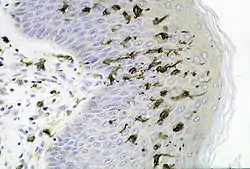

![]() Dendritic cells in skin | |